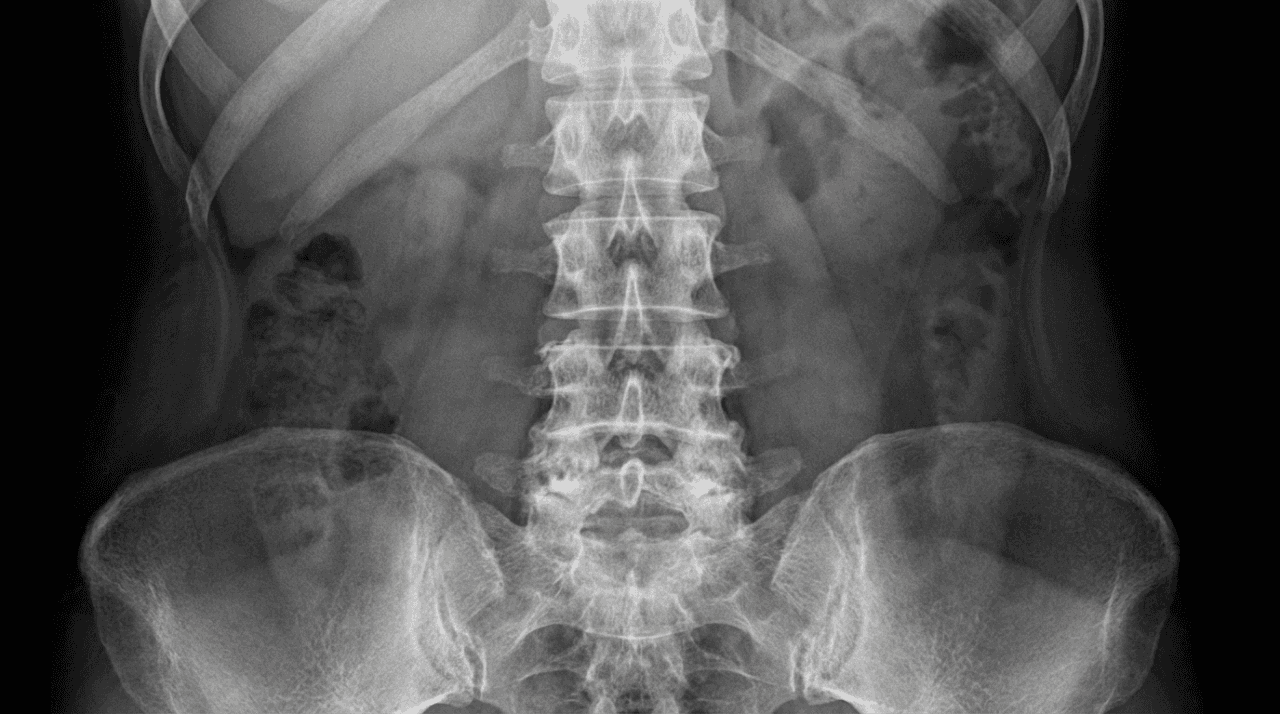

Successful spinal treatment requires precise diagnosis. As a leading consultant spine specialist in Dubai, Dr. Farid utilizes the latest imaging and diagnostic techniques to pinpoint the exact cause of your pain, whether it originates from disc issues, arthritis, or spinal deformities. He offers a full spectrum of care focused on advanced pain management, physical therapy, and strategic non-operative intervention.

Expert Diagnosis and Treatment for Spinal Conditions

Spinal Stenosis: Expert management for severe back pain and leg symptoms caused by the narrowing of the spinal canal, utilizing specialized non-invasive pain relief techniques.